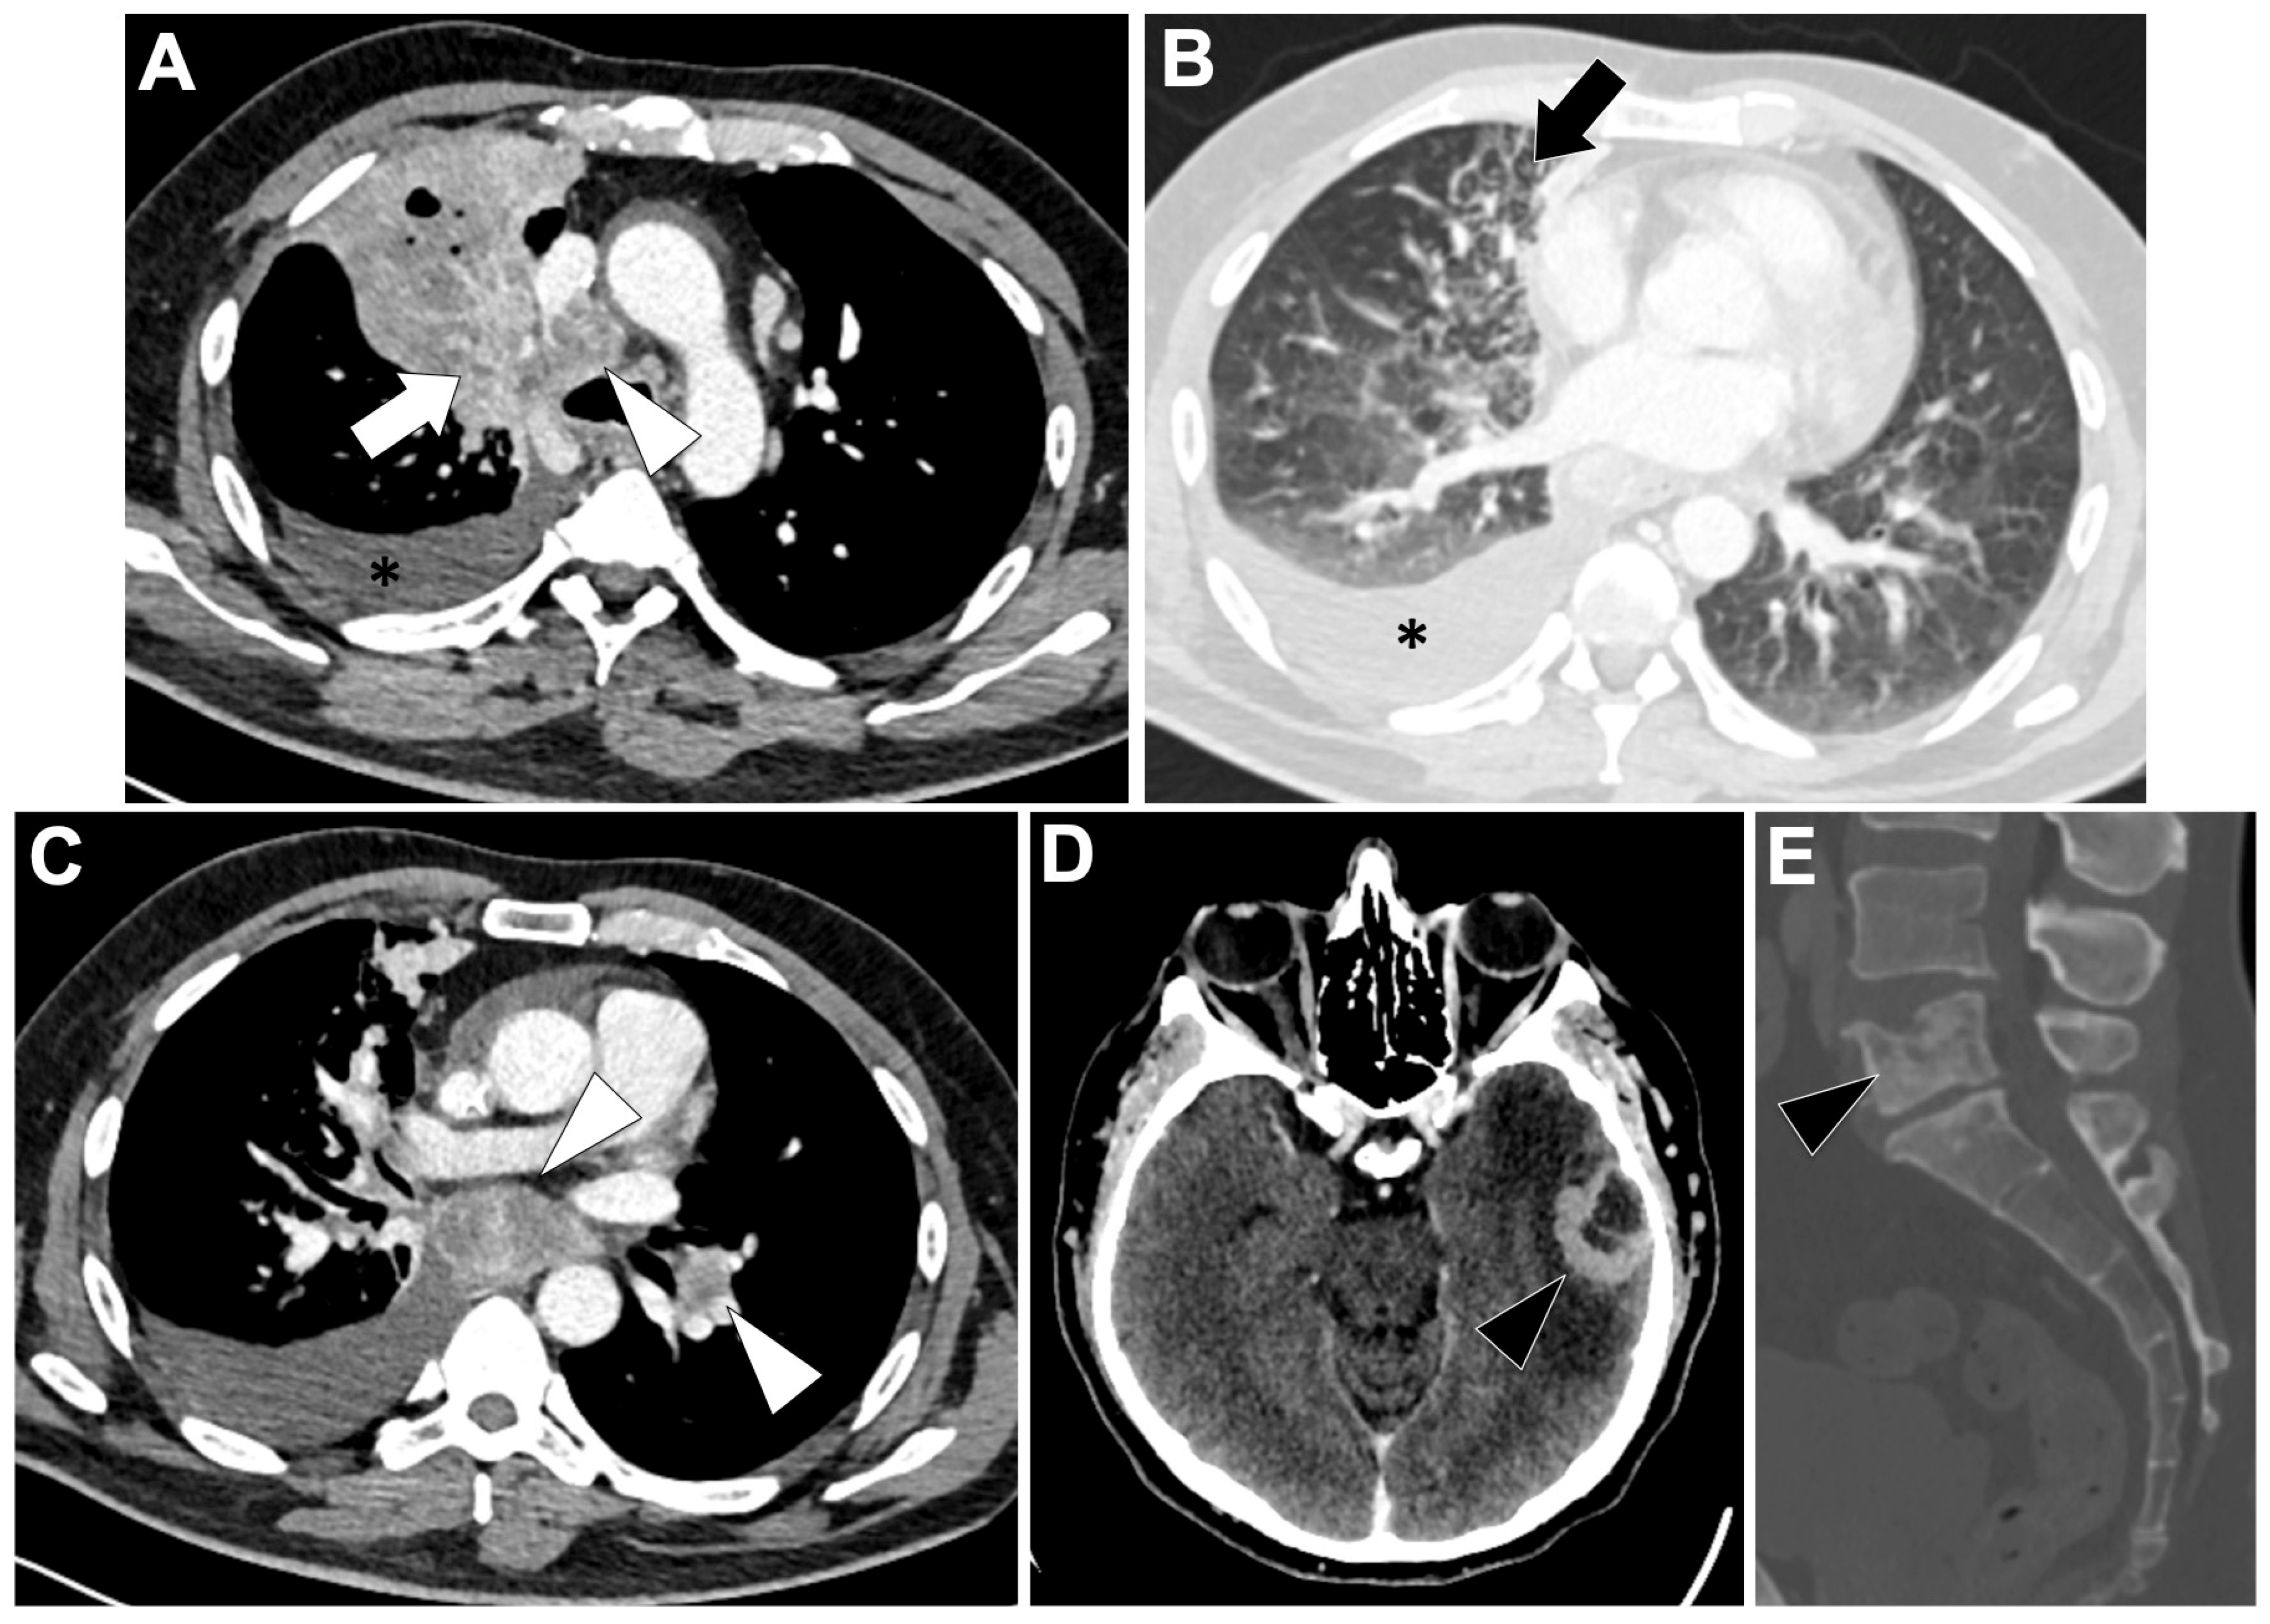

3.5. RET-Altered NSCLC (Figure 5)

3.5.2. Radiological Characteristics of the Primary Lung Lesion in RET-Altered LUAD

3.5.3. Metastatic Pattern in RET-Altered LUAD